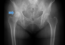

- 股関節痛(目に見えない所で密かに進行)

- シロアリの様ですが、本当にこの表現がピッタリなのです。 軽い…

- 股関節痛(X線に現れてからでは遅い)

- 初期の股関節の問題はX線等には出ません。 X線に出る時は、中…

- 股関節の問題(必ず重心のチェックを)

- 股関節の問題の原因は股関節には存在しません。 それ故に、股関…